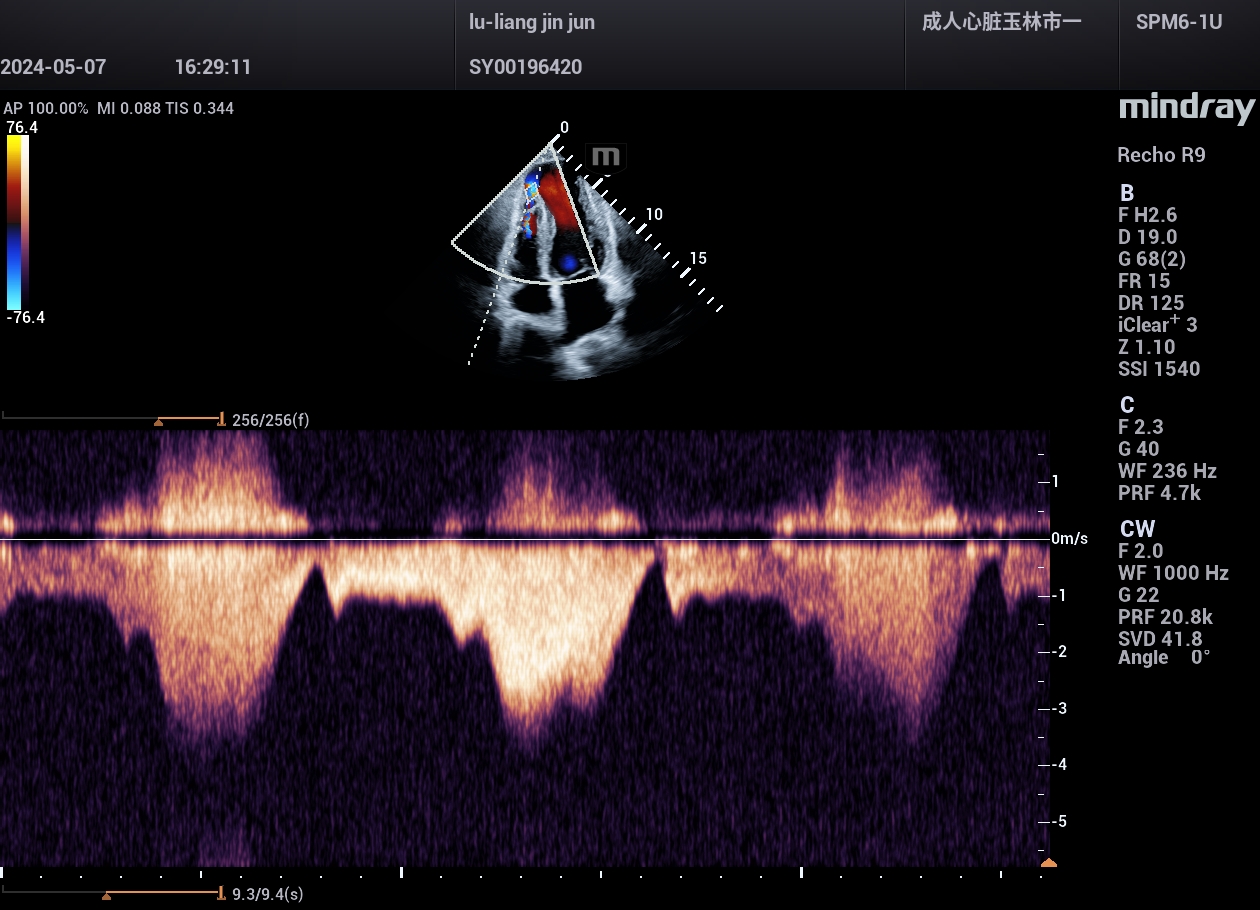

病例,急性心肌梗死,并发室间隔穿孔,迈瑞心脏彩超鲲鹏Recho R9,2024年5月

病例,急性心肌梗死,并发室间隔穿孔。

病例来源,玉林市第一人民医院超声科。

迈瑞心脏彩超鲲鹏Recho R9,2024年5月。

血流显示非常好,灵敏度很高,分辨力很好,流动性连续。